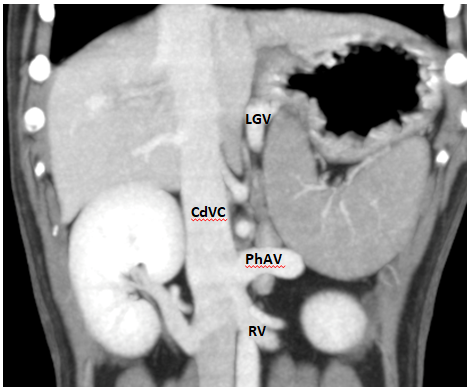

POST-HEPATIC ENTRANCE

(Caudal Vena Cava entrance)

Does the Shunt enter the Phrenic vein or the Left Hepatic Vein?